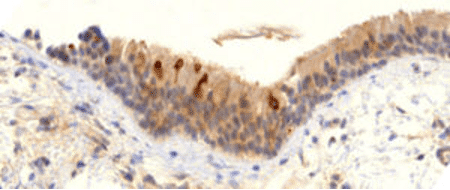

Vaktsiini poolt indutseeritud piigivalgu ekspressioon bronhiaalses biopsias üheksa kuud pärast vaktsineerimist

Slaidil on näha bronhide limaskesta proov patsiendilt, kes on elus, kuid kellel on vaktsineerimisest saadik olnud hingamisteede sümptomid. Me näeme kõige ülemises rakukihis mitut rakku, mis ekspresseerivad tugevalt oga-valku – ja seda isegi üheksa kuud pärast tema viimast vaktsiinisüsti! Kuigi see on tõepoolest kõige äärmuslikum pikaajalise ekspressiooni juhtum. Leidub tõendeid nii Burkhardti lahkamistest kui ka avaldatud uuringutest vereproovide [7] või lümfisõlmede biopsiate [8] kohta, mis näitavad, et ekspressioon kestab mitu kuud.